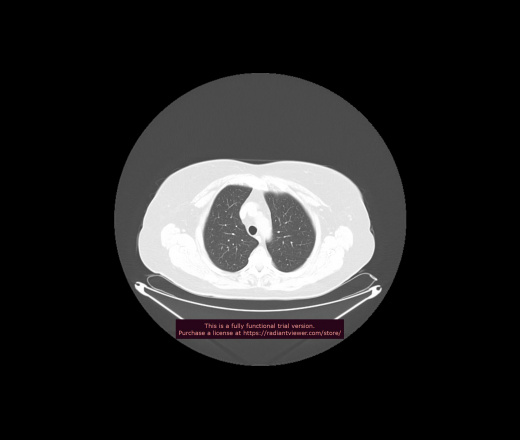

Уважаемые коллеги, если имеется интерес, сможете ли Вы спрогнозировать дальнейшее +-одинаковое течение процесса у 4 данных разных пациентов? Зацепиться где-то можно очень просто, где-то нельзя.